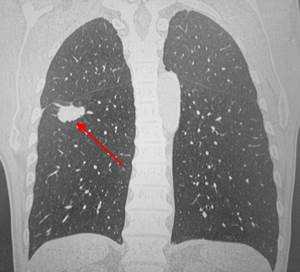

КТ: метастазы в легких при раке молочной железы. На изображении справа красной звездочкой отмечен опухолевый узел в молочной железе, красными стрелками - область прорастания опухоли в грудную стенку. Синими звездочками отмечен карциноматозный плеврит — скопление жидкости в плевральной полости. Слева стрелкой отмечен вторичный узел.